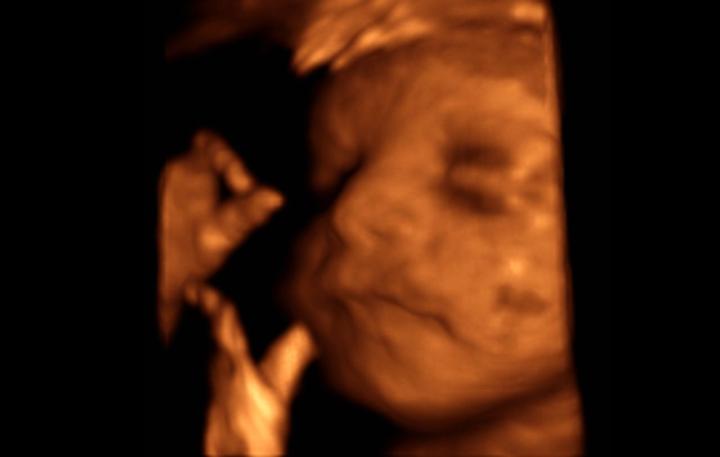

tak zítra nás čeká 3D ultrazvuk 🙂